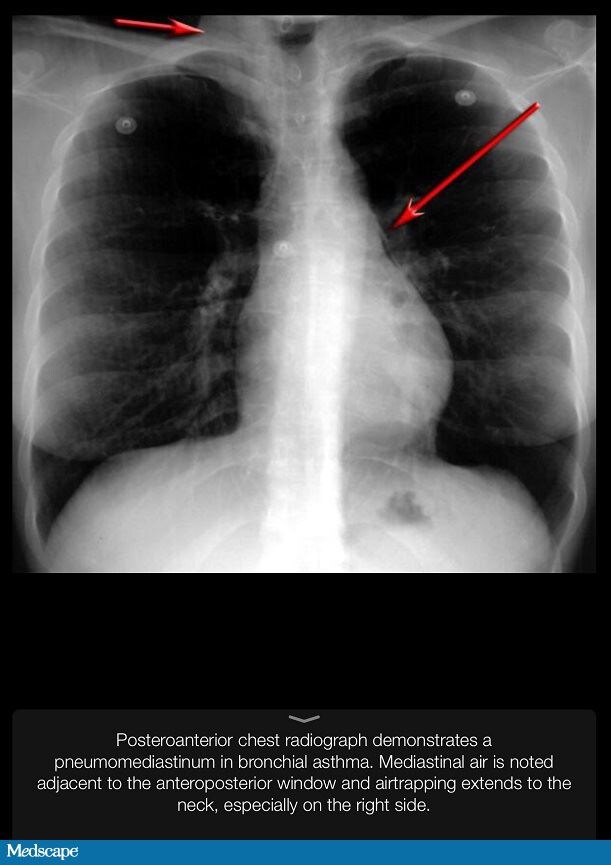

From reference.medscape.com

A 43YearOld Woman With Dyspnea, Cough, and Chest Tightness Cough With Tight Chest The most common symptom of acute bronchitis is coughing with or without mucus. Cough, fatigue, a heavy tightness in the chest. There is no cure for asthma, but. Shortness of breath and wheezing. Symptoms of acute bronchitis last less than 3 weeks. It could be bronchitis, pneumonia or just a simple cold. It could be bronchitis, pneumonia or just a.. Cough With Tight Chest.